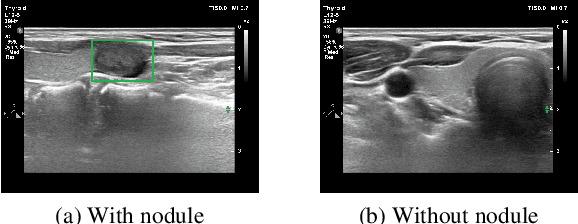

Abstract:The ability to explain the prediction of deep learning models to end-users is an important feature to leverage the power of artificial intelligence (AI) for the medical decision-making process, which is usually considered non-transparent and challenging to comprehend. In this paper, we apply state-of-the-art eXplainable artificial intelligence (XAI) methods to explain the prediction of the black-box AI models in the thyroid nodule diagnosis application. We propose new statistic-based XAI methods, namely Kernel Density Estimation and Density map, to explain the case of no nodule detected. XAI methods' performances are considered under a qualitative and quantitative comparison as feedback to improve the data quality and the model performance. Finally, we survey to assess doctors' and patients' trust in XAI explanations of the model's decisions on thyroid nodule images.